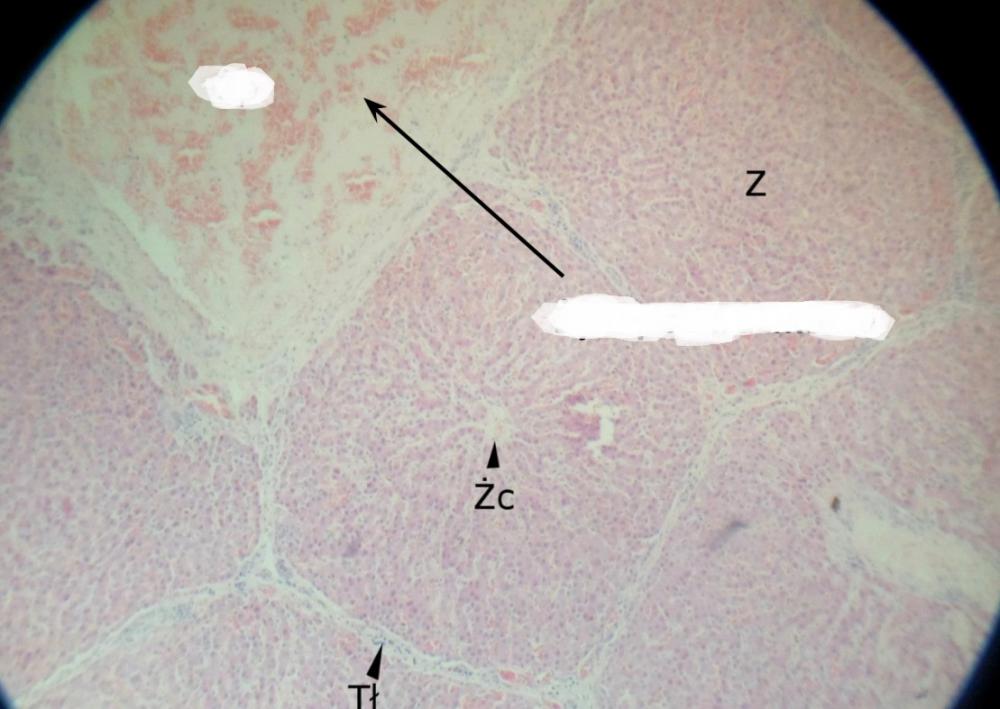

Pytanie 441

żyła centralna (wątroba świni)

Pytanie 442

żyła podzrazikowa (wątroba świni)

Pytanie 443

lokalizacja triad (wątroba świni)